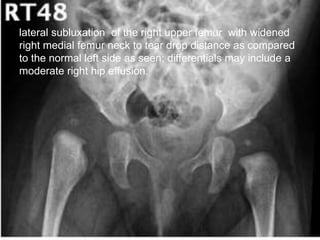

Plain x ray

1]Early Stage – Normal

Look for soft tissue swelling, loss of tissue planes,

widening of joint space and slight subluxation due to fluid in

joint.

2] Late stage – Narrowing and irregularity of joint space,

erosion of epiphysis or metaphysis , ostiporosis

lateral subluxation of the right upper femur with widened

right medial femur neck to tear drop distance as compared

to the normal left side as seen; differentials may include a

moderate right hip effusion.

Imaging Plain x ray 1]EarlyStage – Normal Look for soft tissue swelling, loss of tissue planes, widening of joint space and slight subluxation due to fluid in joint. 2] Late stage – Narrowing and irregularity of joint space, erosion of epiphysis or metaphysis , ostiporosis 3]Plain film findings of superimposed osteomyelitis may develop (periosteal reaction, bone destruction, sequestrum formation).

• 44.

On right side: a large effusion with displaced fat planes, early destruction of the right femoral epiphysis with subluxation. There is irregularity of the metaphysis (infection crosses growth plate) and also irregularity of the acetabular roof

• 45.

Interval radiograph after2 weeks shows more marked destruction of the right femoral head epiphysis.

• 46.

lateral subluxation ofthe right upper femur with widened right medial femur neck to tear drop distance as compared to the normal left side as seen; differentials may include a moderate right hip effusion.